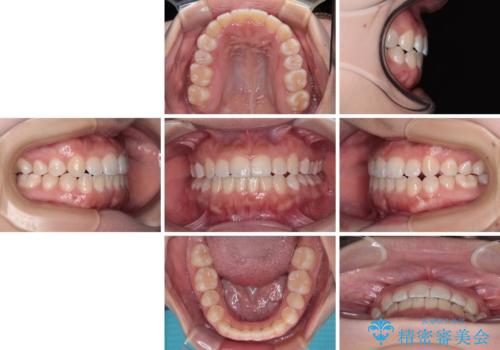

- 上下前歯のクロスバイトと叢生を気にして来院された患者様です。

インビザラインでの治療を希望されていて、デコボコの程度が中等度であり、安価なパッケージにて対応可能と判断されたため、インビザライン・モデレートを用いて矯正治療を行うこととしました。